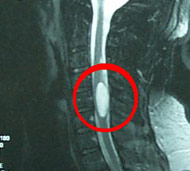

Інтрадурально-екстрамедулярні пухлини. Ці пухлини розвиваються у твердій мозковій оболонці спинного мозку (менінгіоми), в нервових корінцях, що виходять із спинного мозку (шванноми і нейрофіброми) або біля основи спинного мозку (епендимоми кінцевої нитки). Менінгіоми частіше розвиваються у жінок у віці від 40 років і старше. Вони практично завжди бувають доброякісними, їх нескладно видалити, але вони інколи можуть рецидивувати. Пухлини корінців нервів є звичайно доброякісними, хоча нейрофіброми при тривалому зростанні і великих розмірах пухлини можуть перерости у злоякісні. Епендимоми, розташовані в кінці спинного мозку, часто мають великий розмір, їх лікування може бути ускладнене зрощенням пухлини з корінцями кінського хвоста.

Спинальна магнітно-резонансна томографія (МРТ). Замість радіаційного випромінювання в МРТ використовуються потужні магнітні і радіохвилі для отримання зображення поперечного перерізу хребта. МРТ чітко відображає спинний мозок і нерви і забезпечує краще зображення пухлин кісток, ніж комп'ютерна томографія (КТ). Вам можуть ввести в вену кисті або передпліччя контрастну речовину, яка висвітлює деякі пухлини. Крім цього, використовують сканери з високою інтенсивністю сигналу для виявлення невеликих пухлин, які можна не помітити.